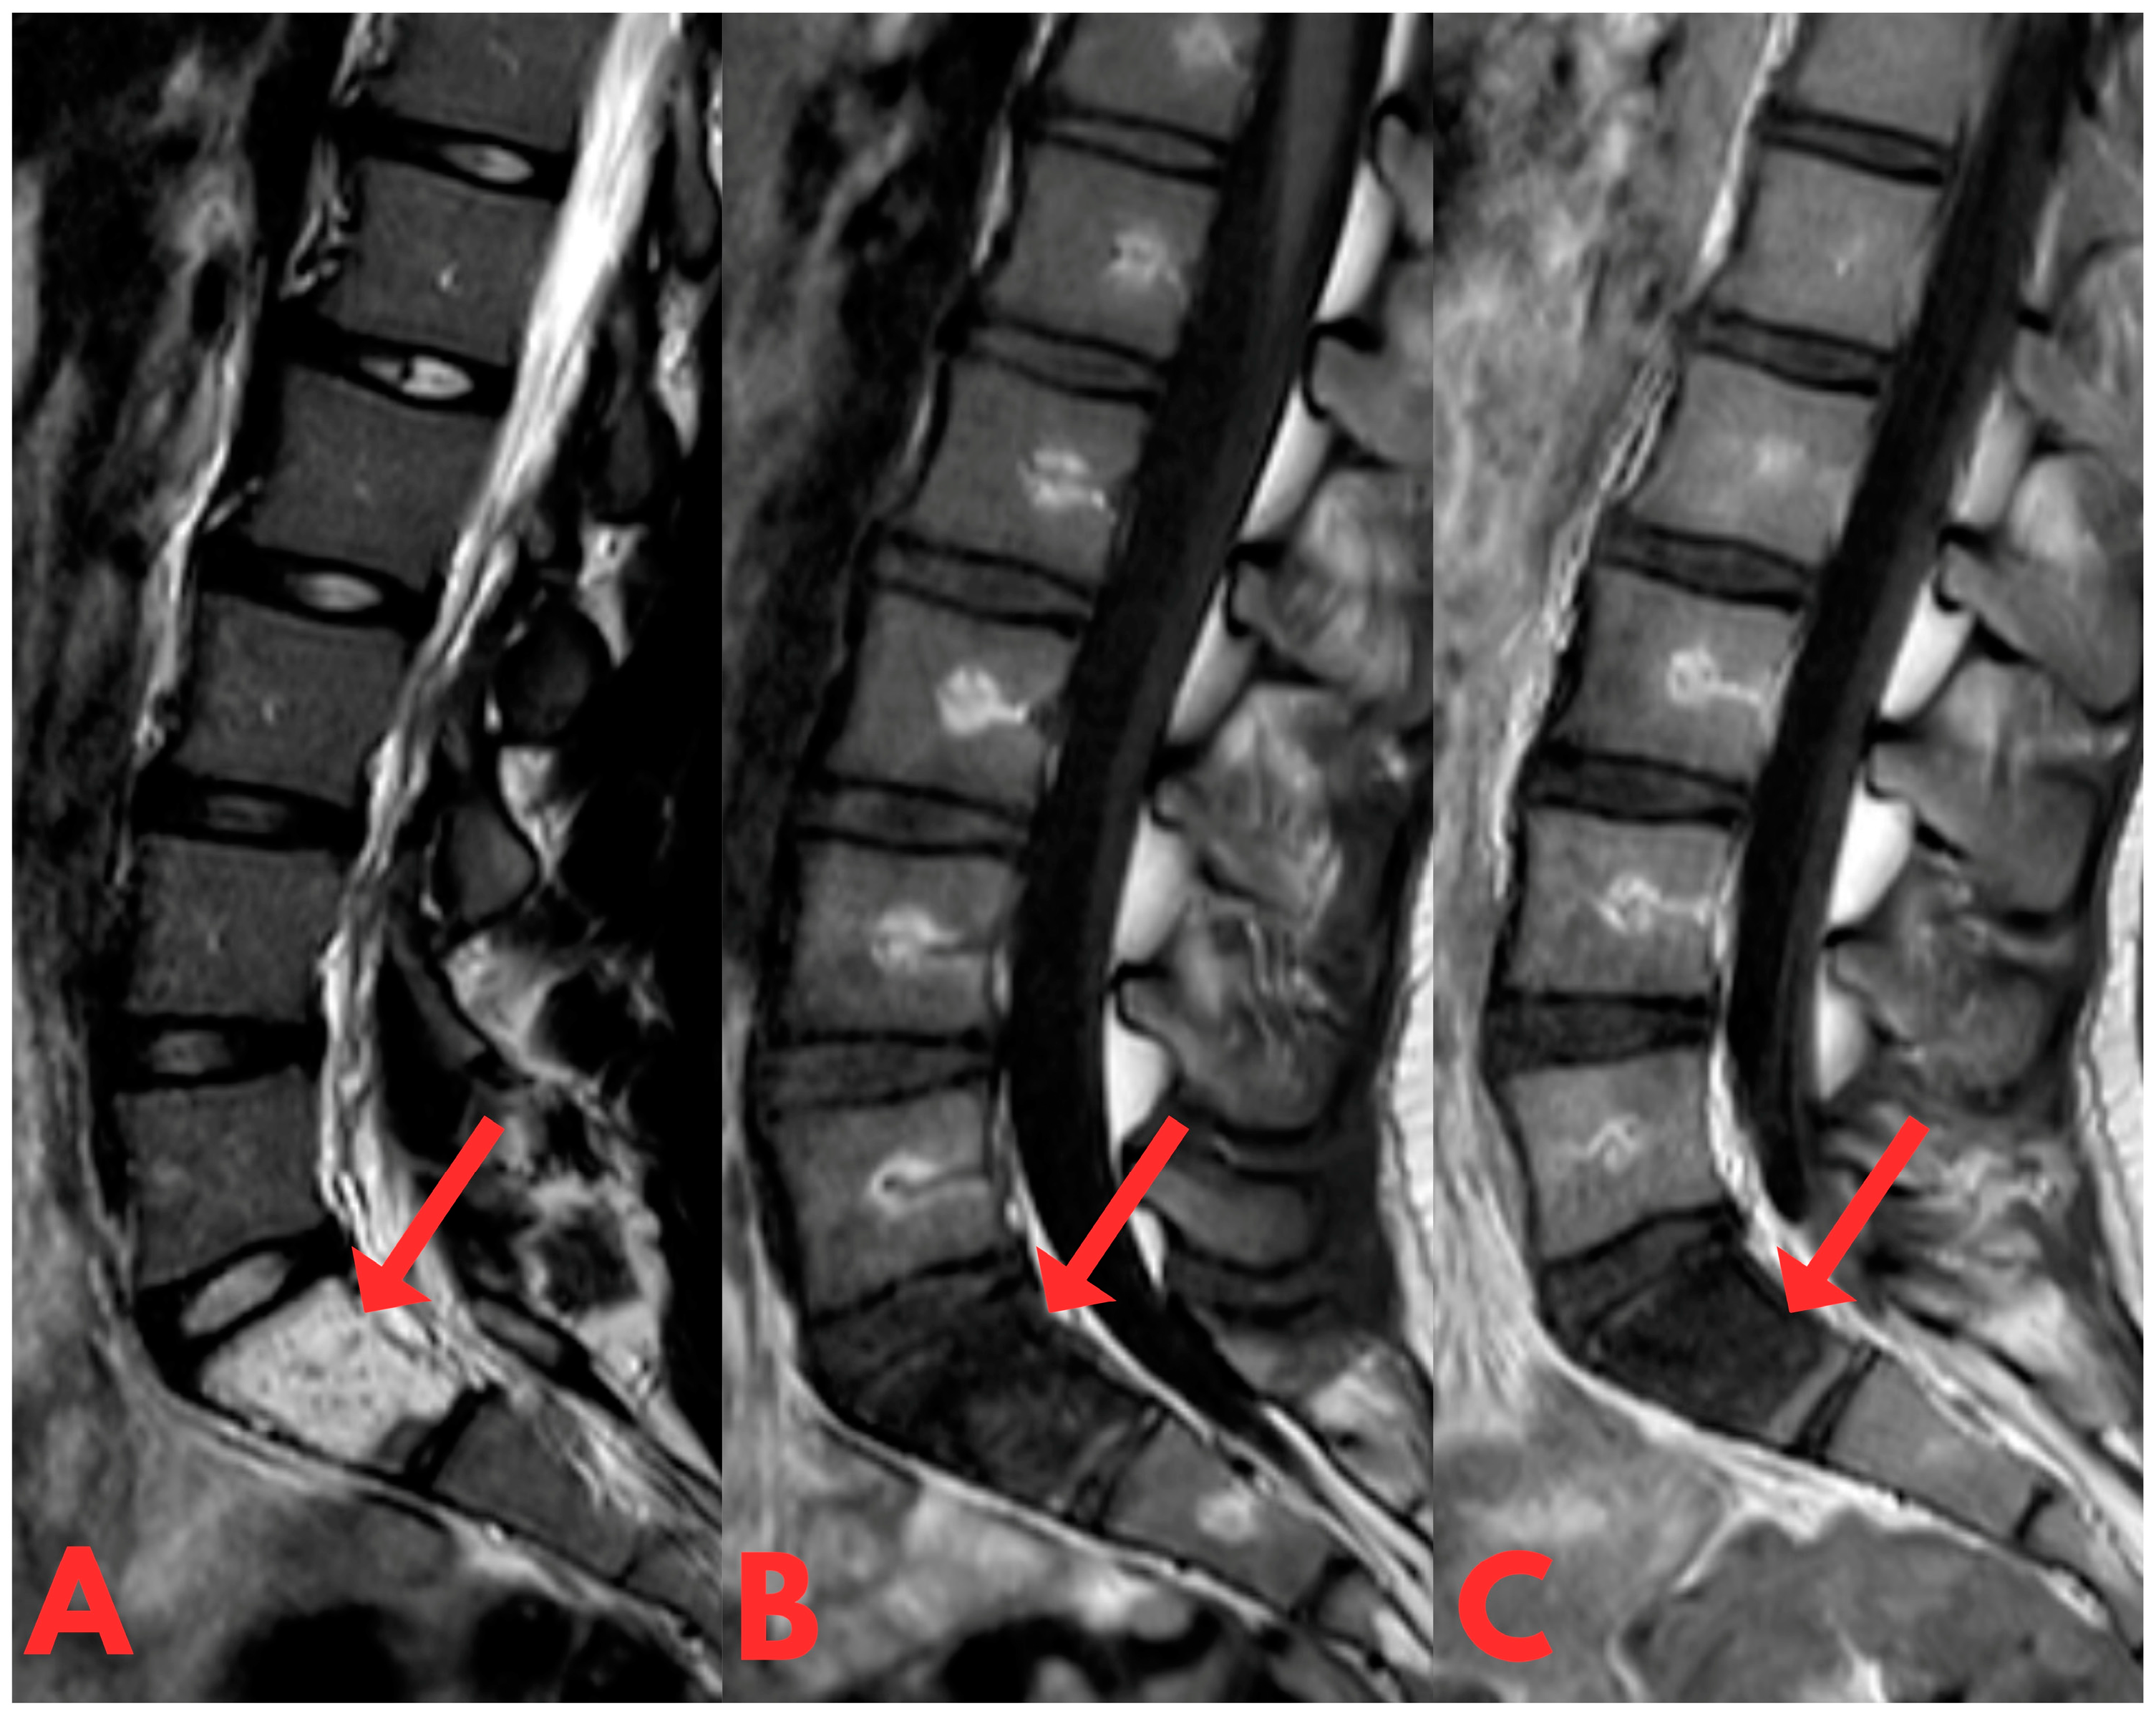

Subsequently, a contrast-enhanced MRI examination of the lumbar spine revealed a centrally located sclerotic lesion with a hyperintense signal on T2 and hypointense on T1, measuring 2 × 4 cm in the corpus of the S1 vertebra (Figure 2). Imaging characteristics were indicative of fibrous dysplasia due to its characteristic features on MRI examination (T1: usually intermediate to low heterogeneous signal; T2: variable signal [8,9]), with a differential diagnosis of osteoid osteoma or another benign lesion.

Figure 2.

First T1- and T2-weighted sagittal contrast-enhanced MRI of the lumbar spine (T2W_TSE, T1W_TSE, T1W_TSE c+ sag) showing a sclerotic lesion with a hyperintense signal on T2 (A) and hypointense on T1 (B,C), which occupies practically the entire body of the S1 vertebra. Spread is not seen to the anterior epidural space or the prevertebral space.